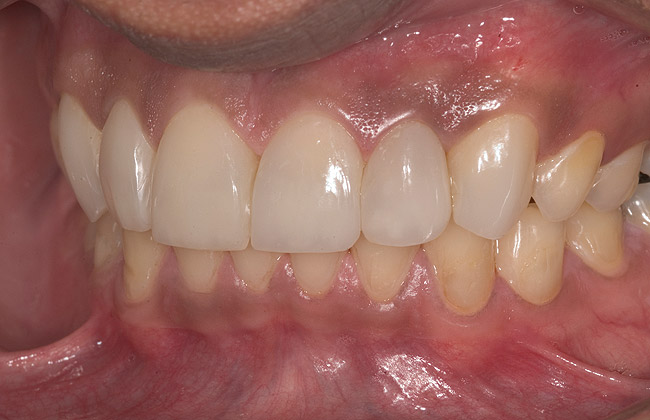

Figure 14  Postoperative smile.

Figure 14

Figure 15  Maximum intercuspation (MIP) after restoration of the lost palatal anatomy.

Figure 15

Figure 16  1:2 right lateral view; posteriors discluded in MIP.

Figure 16

Figure 17  1:2 left lateral view; posteriors discluded in MIP.

Figure 17

Figure 18  1:1 view of restored palatal surfaces with nanofilled resin.

Figure 18

White enamel shade was placed on the putty index and carried to the palatal surface of No. 9. This layer was spread uniformly and thinned out and spread along the entire width of the tooth (Figure 11). After curing this layer, A2 dentin was layered to simulate the lobular pattern seen in dentin of the natural teeth (Figure 12). After curing, a layer of transparent resin was placed in the incisal areas between the dentinal lobes. The final layer of A2 enamel was built and shaped to full contour (Figure 13). A similar build-up was done for all the remaining anterior teeth. The bite in MIP was adjusted such that there was uniform contact on all anterior teeth. The anterior guidance was harmonized to maintain uniformity in the contact of the incisors during protrusion and the canines and incisors during lateral excursions. Finishing and polishing was done per protocol (Figure 14 through Figure 18).13